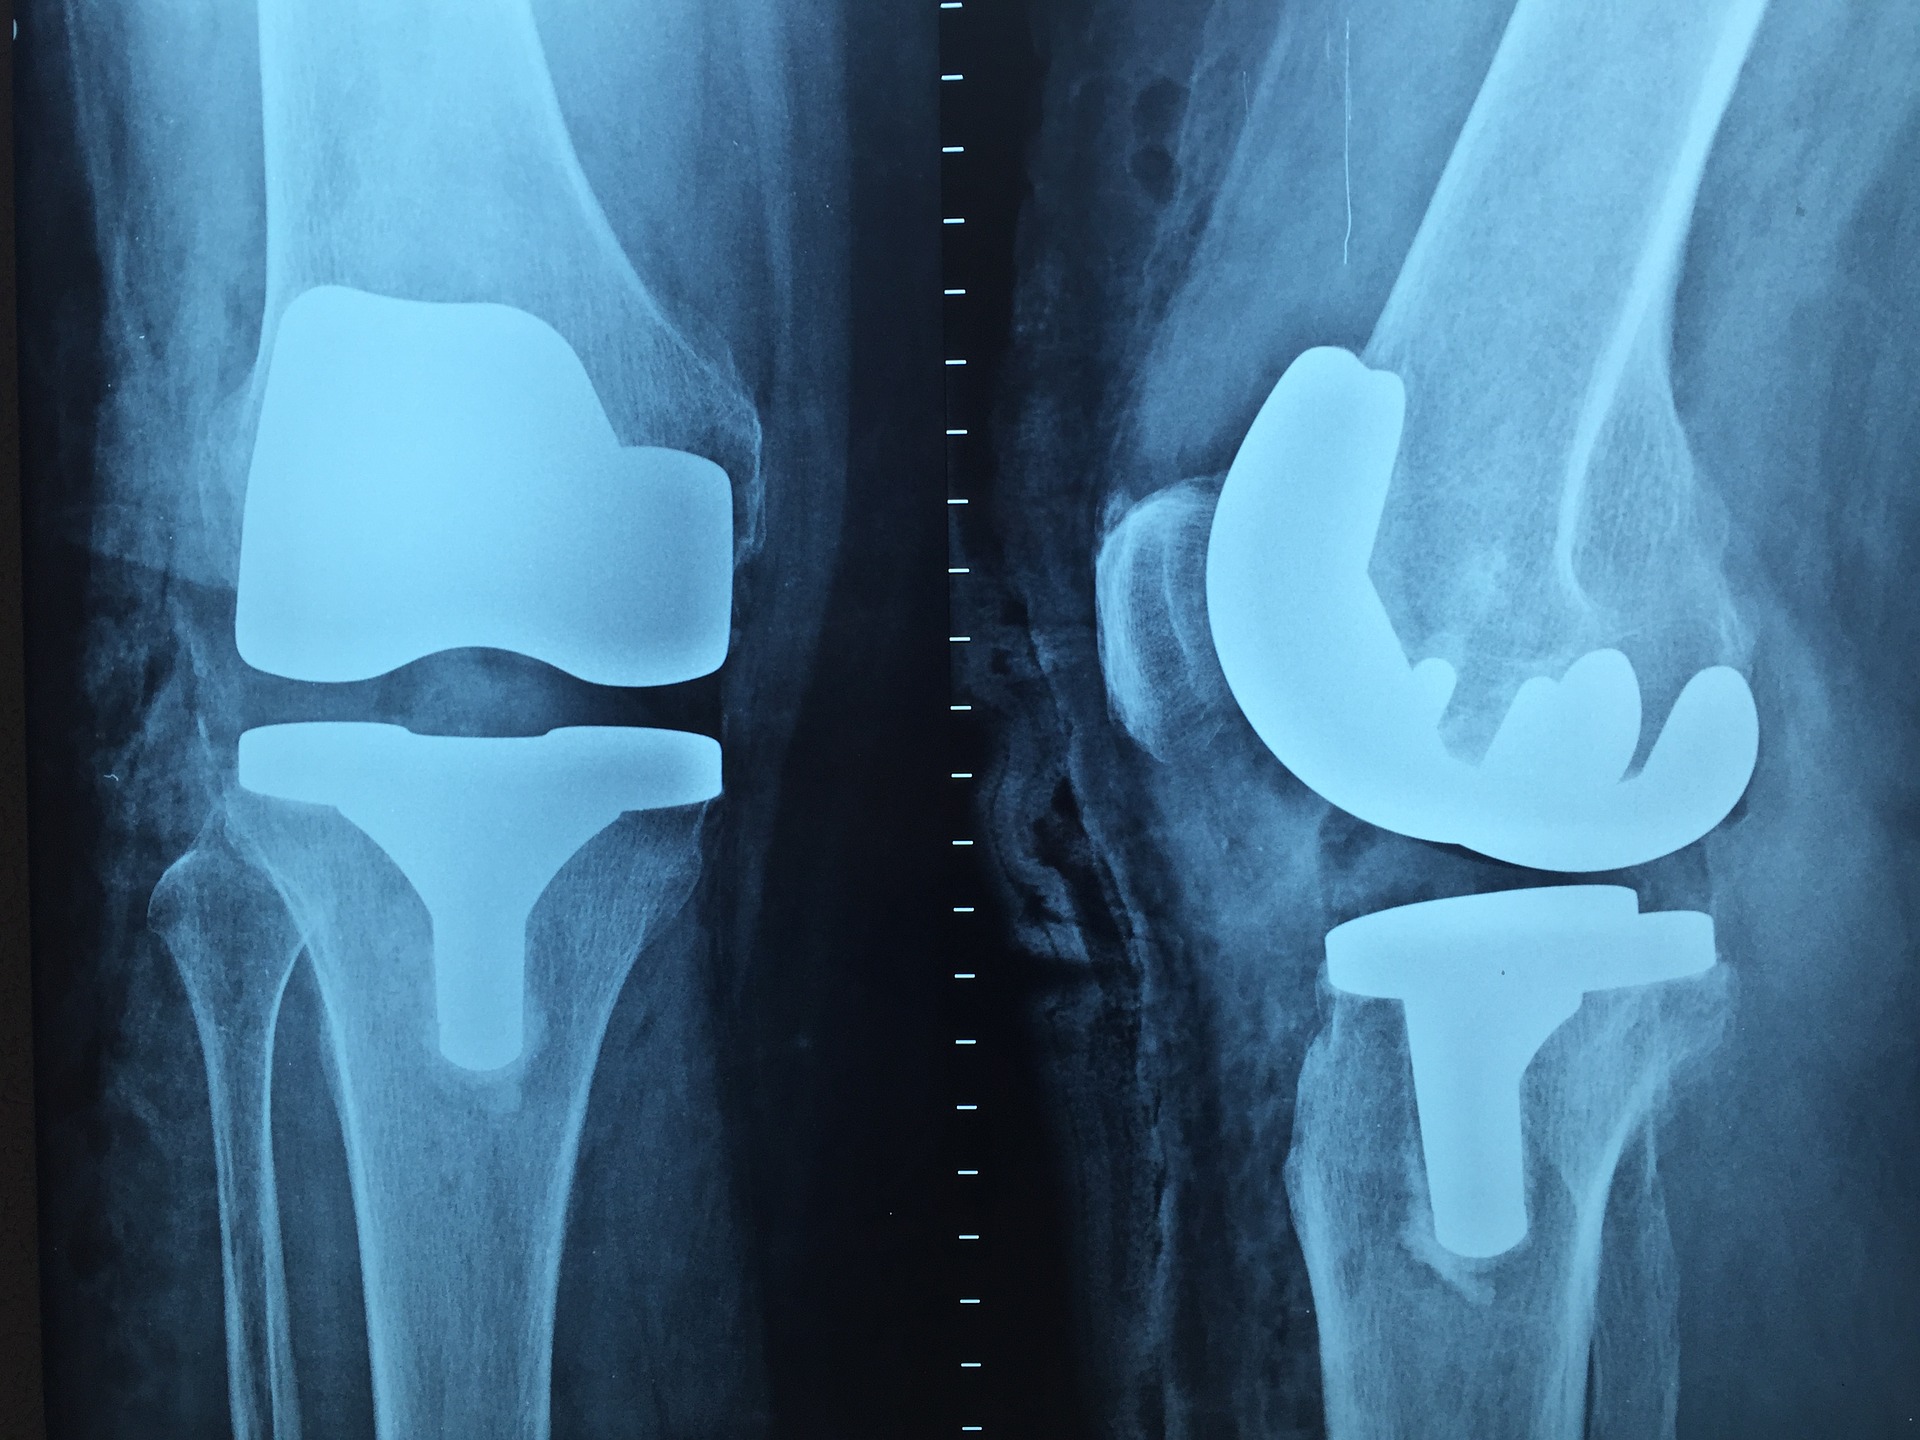

Uszkodzenia ścięgien są niezwykle uciążliwe. Przydarzyć się to może zarówno sportowcom jak i osobom aktywnym …